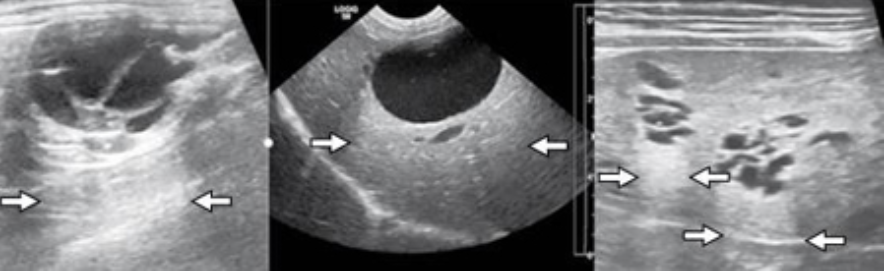

Reverberation (Ring Down)

highly reflective surfaces

sound waves bounce back and forth - produce echoic lines at regular intervals

commonly caused by gas or free air

Comet Tails

type of reverberation artifact seen with gas interfaces

smaller width strong lines produced

air pockets in GI tract or metallic objects, a foreign body, or tip of a biopsy needle